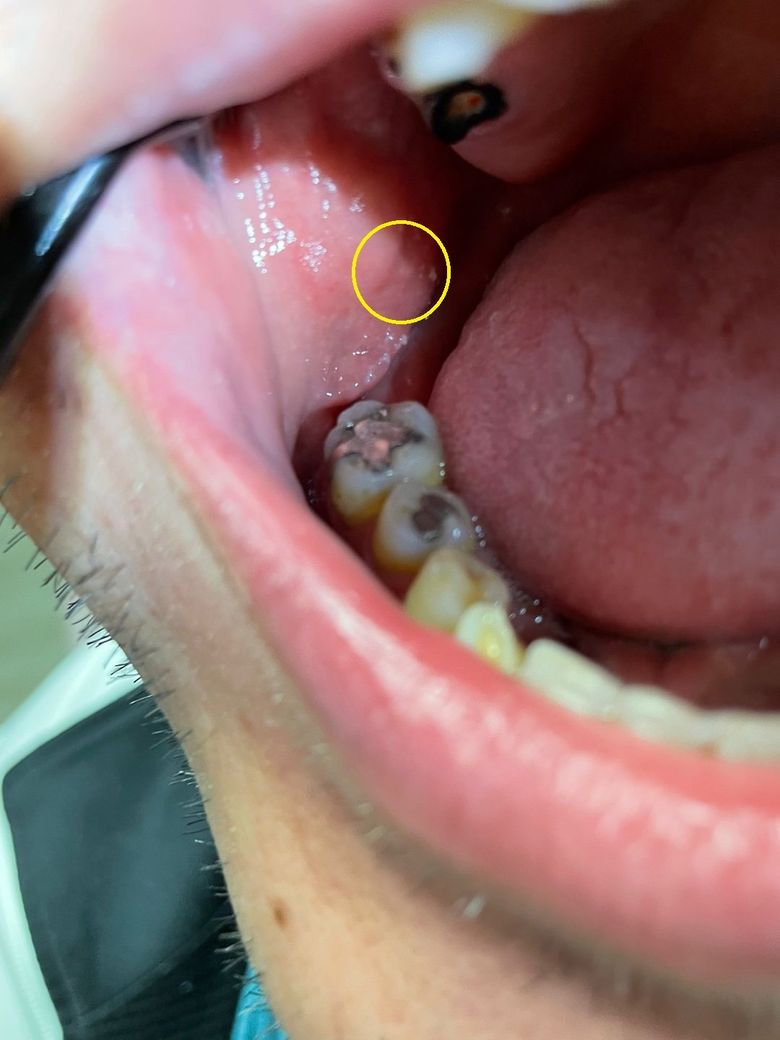

그리고 상처가 잘 아물고 있는건지도 알고 싶네요

볼점막은 제가 볼땐 쌔게 씹어서 생긴 자국으로 보여지긴 합니다

통증도 없고 커지거나 하지 도 않고 있습니다

• 2번 째 사진

사진으로 보기에는 볼점막이 씹힌 흔적이가나 볼점막이 치아면에 닿아 압박을 주면서 생긴 흔적으로 보입니다.

어느 것이거나 그냥 두면 저절로 없어집니다.

사진으로만 본다면 치아자국인것으로 보입니다.

위, 아래치아를 씹으면서 볼에 자국이 나는경우는 흔하게 있고 보통 치료를 필요로 하지 않습니다. 감사합니다.

보통 정상적인 분들은 항상 볼 안쪽면에 치아자국이 나와있습니다.

지속적인 자극으로 해당부분이 과각화 되어 하얗게 보이기도합니다.

특별히 통증이 있거나, 피가 나거나 붉게 부풀지 않는 이상 병적인 소견은 아니니 안심하고 지내시면 됩니다.

볼점막이 치아에 씹혀서 생긴 상처나 자국같습니다. 시간이 지나면 괜찮아 지실꺼니 너무걱정은 안하셔도 됩니다. 당분간은 자극적인 음식은 피해주시면좋습니다